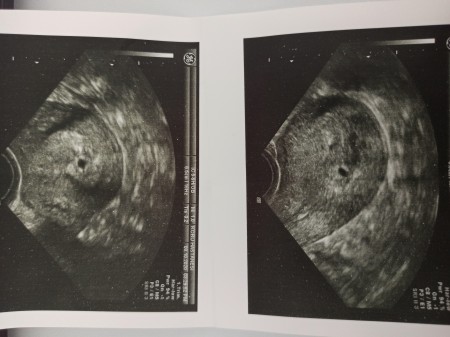

Merhaba hanımlar hamile olduğumu öğrendiğimde 29 eylülde  beta 55 çıktı ayın 8 tekrar kan verdiğim de beta 2032 çıktı doktor normalde bu değerde kesmeyi görmemiz gerekiyor ama nadirde olsa görülmeye bilir dedi profile resim koydum siyah bir nokta var biraz aşağıda bir tık yukarı da olsa kese diyicem dedi ama bebek oraya tutunacak korkma falan dedi dış gebelikten de şüphe ediyor pazartesi tekrar kontrol Gidicem böyle bir durum yaşayan var mı

Dış gebelikte kese zaten rahim içinde olmaz. Ultrason fotoğrafınızda küçükte olsa gözüken kese gibi geldi bana

İşte doktorun aklına takılan tek nokta biraz aşağıda olması

Dış gebelikte kese gözükmez senin ki görünmüş o nokta olan kese canım

O ortada siyah yuvarlak şey kese ışte canım